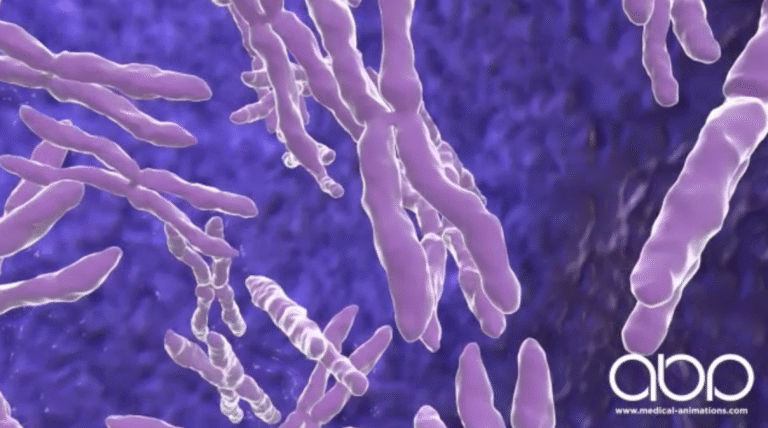

Every story begins with a single thread. For biology, that thread is DNA – an intricate code coiled into the chromosomes